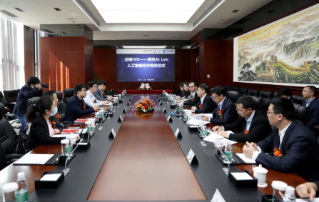

![mindray-and-tencent-ai-lab-collaborates-on-intelligent-morphology-solution.thumb.319.319 Mindray y Tencent AI Lab colaboran en una soluciĂłn de morfologĂa inteligente]() Mindray y Tencent AI Lab colaboran en una soluciĂłn de morfologĂa inteligenteMindray y Tencent AI Lab firmaron un acuerdo marco de colaboraciĂłn en materia de IA con el objetivo de desarrollar conjuntamente productos asistidos por IA para el anĂĄlisis de cĂ©lulas sanguĂneas y explorar la integraciĂłn y aplicaciĂłn de las tecnologĂas de IA en el diagnĂłstico in vitro.2021-03-09

Mindray y Tencent AI Lab colaboran en una soluciĂłn de morfologĂa inteligenteMindray y Tencent AI Lab firmaron un acuerdo marco de colaboraciĂłn en materia de IA con el objetivo de desarrollar conjuntamente productos asistidos por IA para el anĂĄlisis de cĂ©lulas sanguĂneas y explorar la integraciĂłn y aplicaciĂłn de las tecnologĂas de IA en el diagnĂłstico in vitro.2021-03-09 -